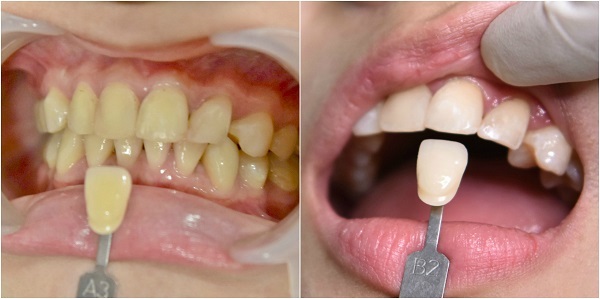

然後是色板對色、接著是牙齦保護程序以及塗抹美白藥劑後用冷光機照射每8 分鐘 一次,